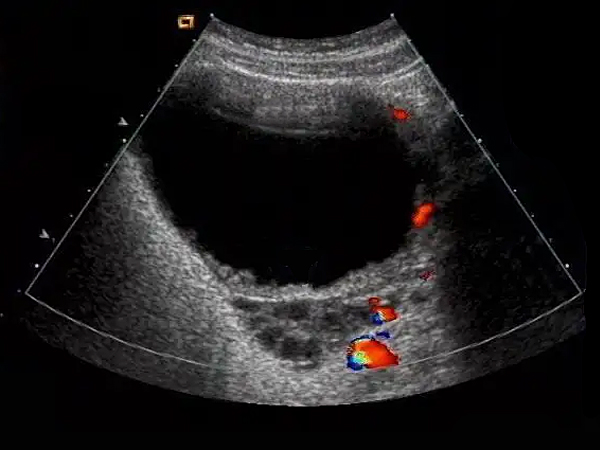

迈瑞超声卵巢成像图

图片尺寸608x453